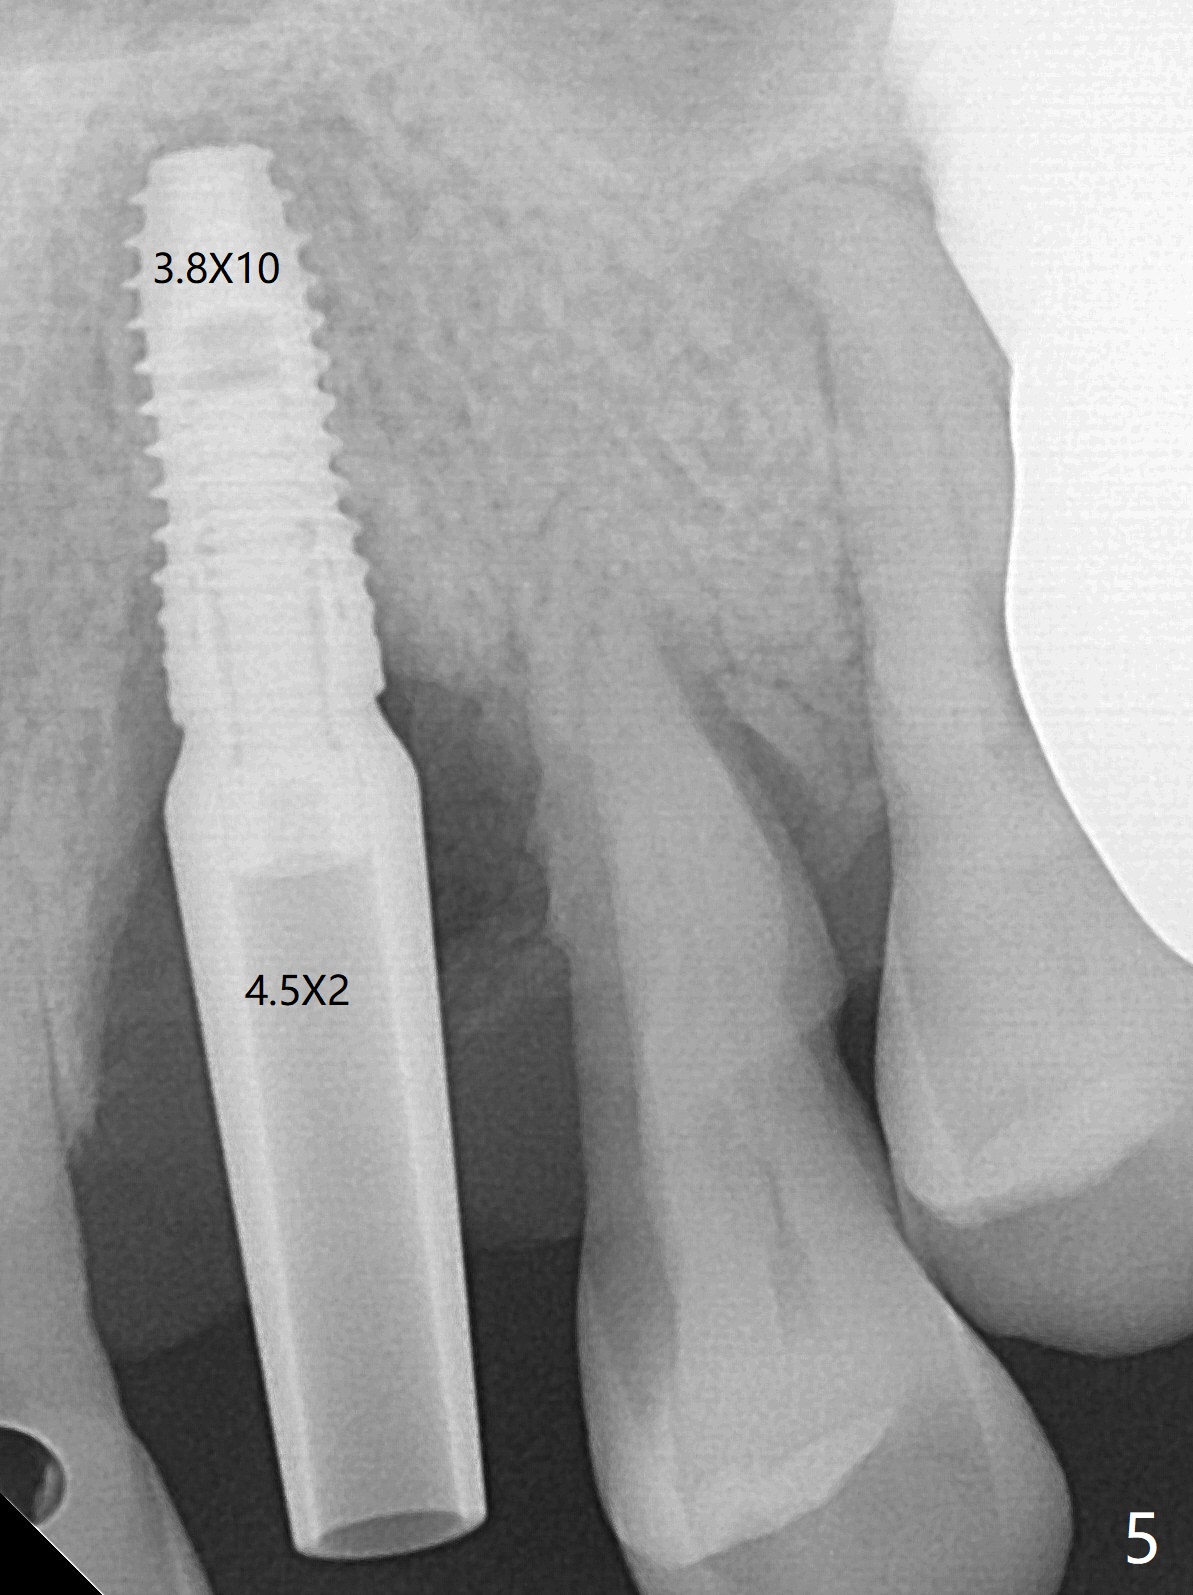

A 62-year-old man with generalized chronic periodontitis returns with chief complaint of loose tooth at #11 (Fig.1). Although a buccal fistula (Fig.1 <) is closer to #12 than to #11, percussion is more severe at #11 than 12. The buccal plate of #11 is missing, but it is possible to place a narrow immediate implant because of the wide alveolus (Fig.2). Since the gingiva is ~ 10 mm long, a mill abutment is to be used (Fig.3,5). In fact the fistula communicates with #11 extraction socket. After debridement, osteotomy is initiated (Fig.4) for a 3.8x10 mm implant ~ 35 Ncm, followed by seating a 4.5x2 mm mill abutment (Fig.5). Abundant sticky bone is placed in the remaining socket (for buccal plate reconstruction) and against the root surface of the neighboring teeth (Fig. 6 * (#10,12)). Finally 2 pieces of PRF membranes are utilized to facilitate repair of the buccal soft tissue defect (Fig.7 *). The root prominence of the canine seems to be maintained by the bone graft (Fig.8 C). Acrylic dressing holding the PRF membranes in place remains in situ with the healthy gingiva buccal (Fig.9) and palatal (Fig.10) 11 days postop. Note the acrylic locking into the undercuts of the neighboring teeth (*). 经过一段摸索发现离心每分钟1500转5分钟后,抽取上清液,接着再离心10分钟剩余上清液就形成血小板块,压制后便是血小板膜,后者似乎有助于软组织愈合,而上清液用来制备骨块,帮助硬组织生长。利用这个原则讨论以下病例治疗。The gingival margin gains ~ 5 mm 6 weeks postop when the acrylic dressing is removed (Fig.11,12 (<: previous one), as compared to Fig.7,8). 治疗结束时尖牙牙龈缘高于第一双尖牙(图七,八),六个星期后,尖牙牙龈缘却低于双尖牙(图十一,十二(箭头:原始牙龈缘))。术后2.5,4.5月基台周围牙龈似乎能与钛合金附着,防止细菌进入深部植体(图十三,十四)。临时牙冠脱落多次,可能与mill abutment太光滑有关,所以颊侧,舌侧磨成平面(图十四)。取模时好像不必取出基台清洗(仿佛没有炎症),原位用树脂延长基台。术后5个月CT显示颊侧骨板再生(图十六-十八)。取模时并没有用树脂加长基台;粘固时,牙冠颜色理想,但是照片中并不是如此(图十九,二十),颊侧骨板没有塌陷。术后11个月基台颊侧骨板没有萎缩(图二十一:B);3d图像:骨壁完全形成(图十六对比:部分形成)。密度也增高(图二十二:B),与术后五个月比较(图十七)。术后十一个月,粘固后五个月角化龈存在(图二十三),牙冠颈部有金属颜色透出,是因为二段式基台太粗了(最细4.5毫米),可以请实验室在牙冠内部涂opaque material而减轻。